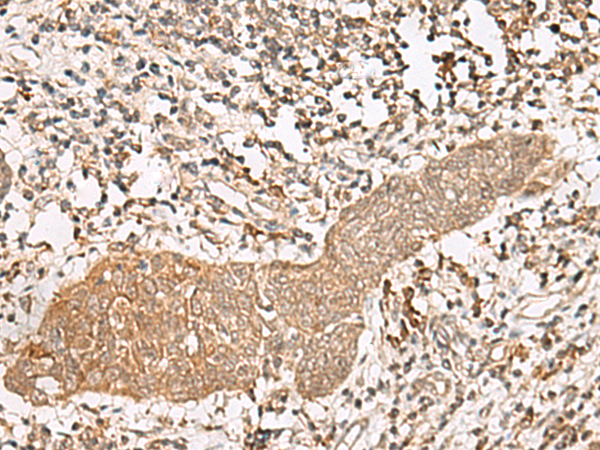

ELISA, IHC |

IHC positive control: |

Human esophagus cancer and Human thyroid cancer |

IHC Recommend dilution: |

40-200 |